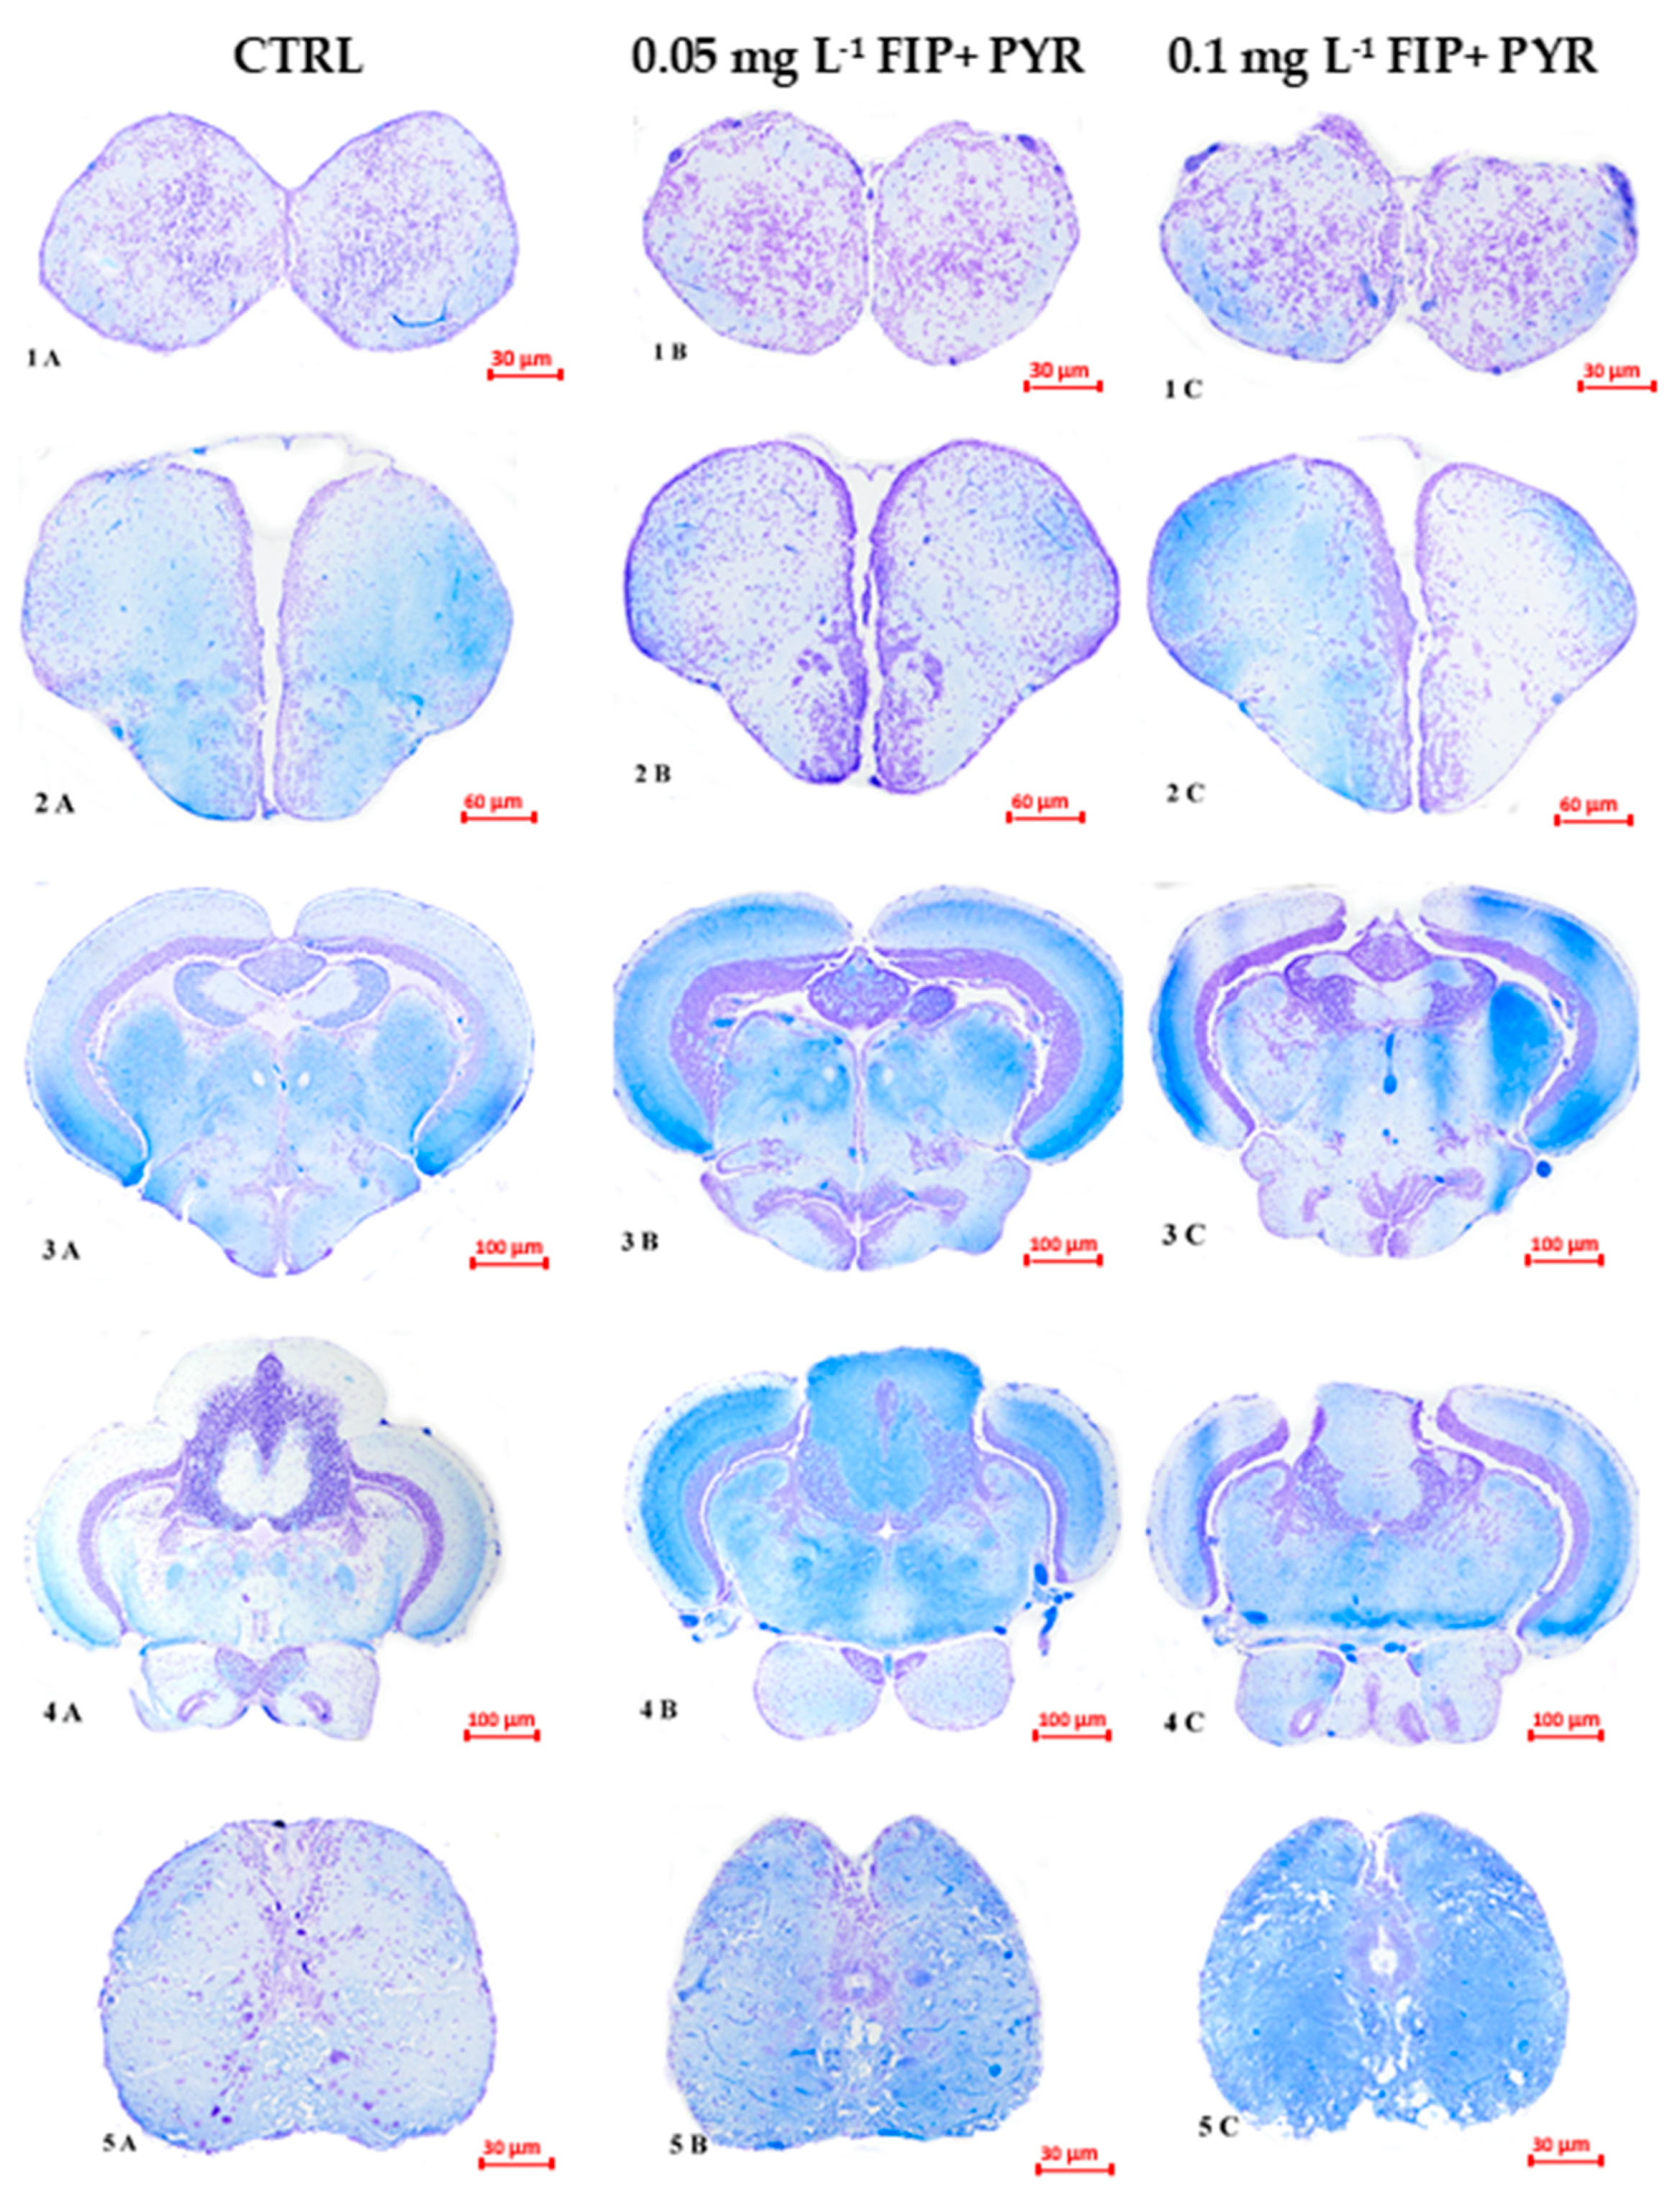

3.3. Histological Alterations

| FIP + PYR | zebrafish Danio rerio | 0.05 and 0.1 mg L−1 5 days | ↑locomotor activity ↑anxiety level ↑hemosiderin deposits dilated blood vessels and leucocyte infiltration in different brain sections | Present work |